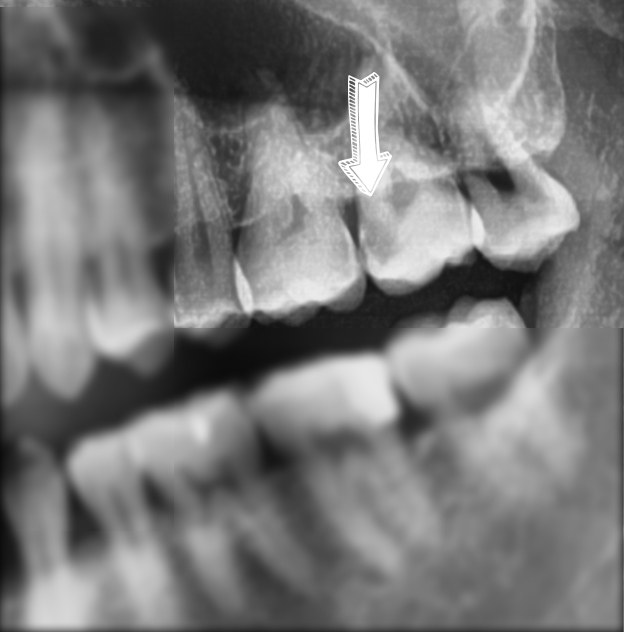

그러던 어느날 그냥 저희 원장님이 이번엔 파노라마 하나 찍어봐~ 해서 찍었는데 충치가 따딴!

매우 치아 신경과 가깝게 충치가 있어서 그 치과의사분(원장님 친구분)도 당황하셨습니다. 치과의사라면 딱봐도 신경치료해야 될 상태였기 때문이죠. 아무 증상이 없었는데도 말이죠.

심지어 이렇게 치아 상에서는 그 부분이 크게 충치가 있는 것처럼 보이지 않는데도 말입니다. X-RAY의 중요성이지요. 이 분 같은 경우는 본인이 치과의사라서 저희 치과에서 정기적으로 엑스레이를 촬영하지 않았지만, 일반적인 환자분들 같은 경우는 정기검진과 정기적인 파노라마나 엑스레이 촬영이 필수입니다. 눈으로만 보는 것으로는 충치검진이 명확하지 않습니다.

이렇게 충치가 치아신경과 근접해 있어 신경치료가 필요한 것입니다.